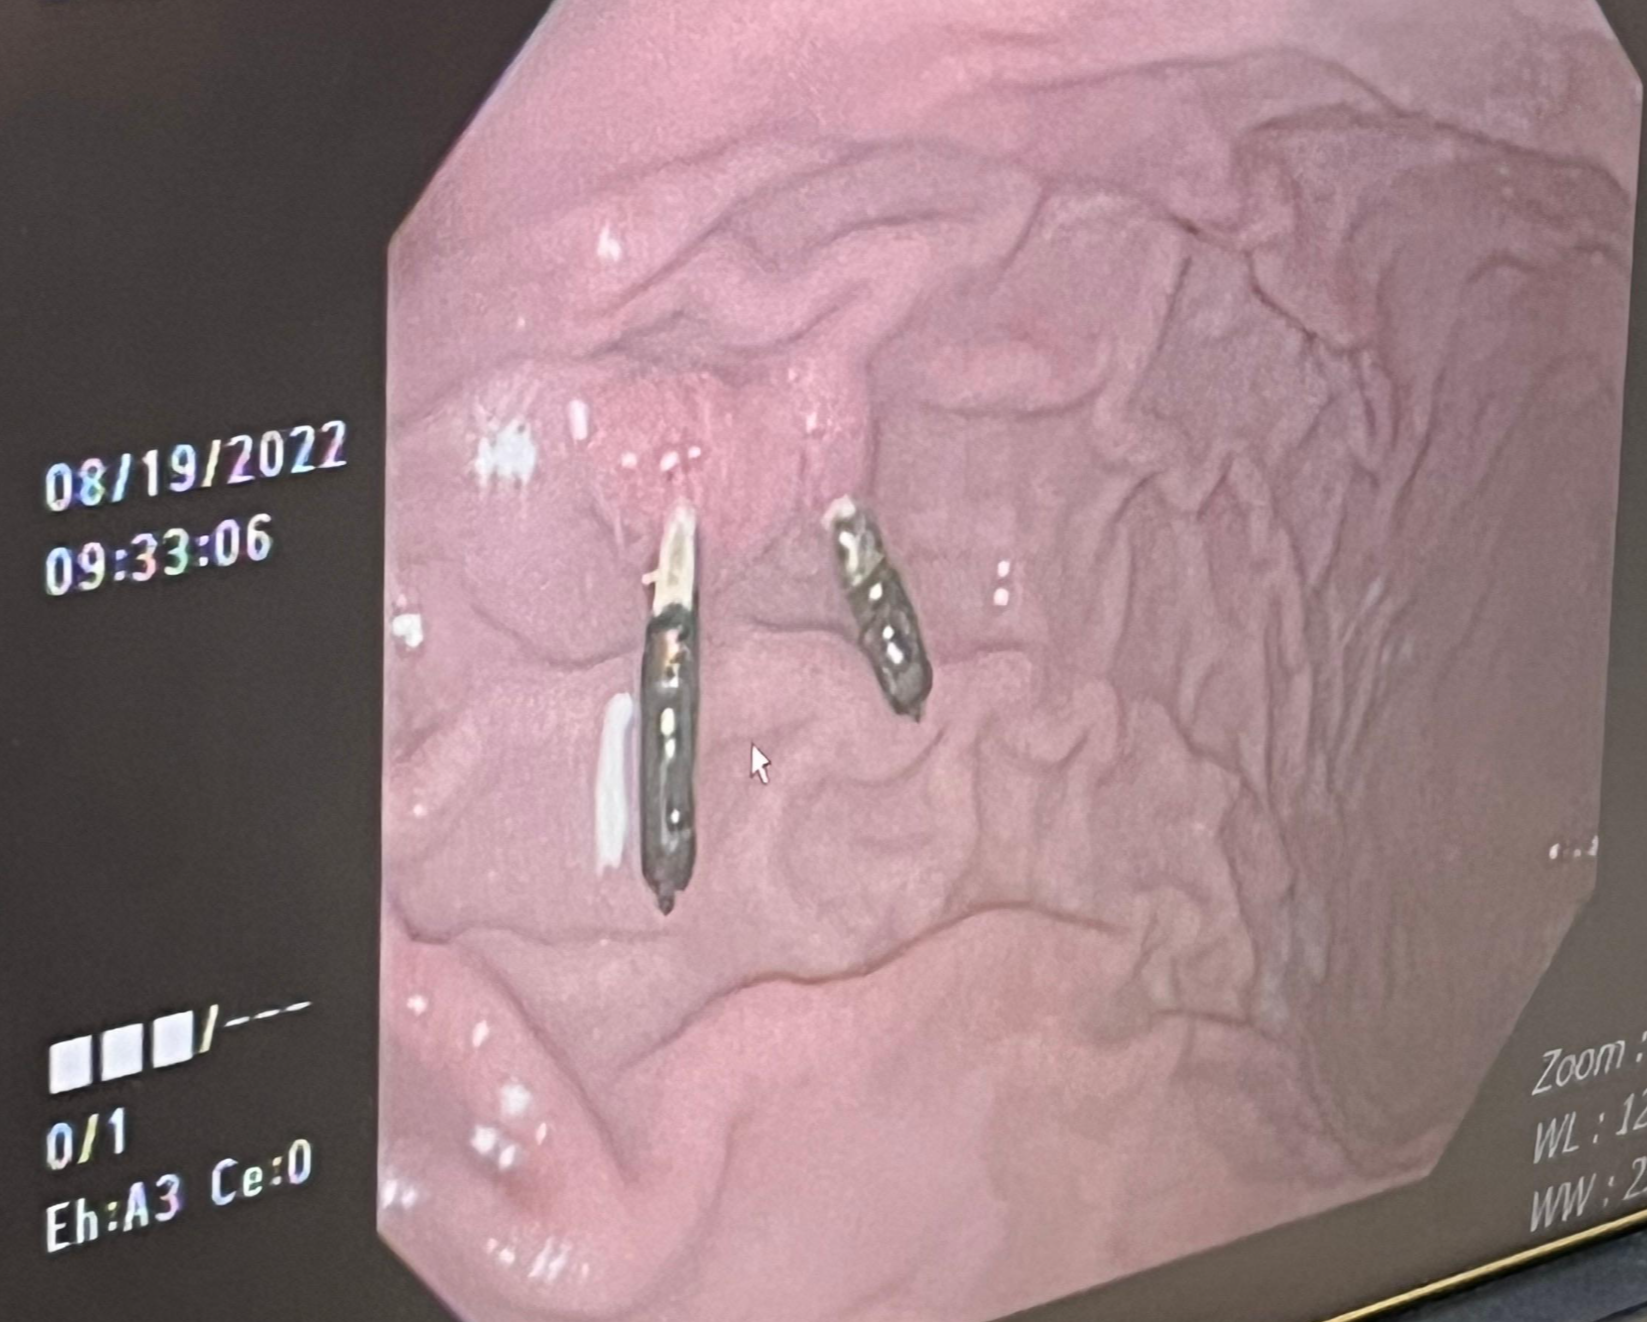

의사샘이 사진을 보여주신다.

대장이 아니고 위에 있습니다!!

이전에 어딘가에서 위내시경하고 용종떼고 지혈하려 막아둔것입니다!

이제껏 그냥 사셨으니 그냥 사셔도 됩니다!